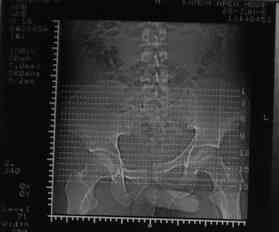

Уважаемые коллеги! На днях оперировал перелом таза месячной давности - разрыв симфиза, перелом обеих ветвей правой лонной кости, трансфораминальный перелом крестца слева. Представляю рентгенограммы с задержкой - технические причины.

Предоперационные рентген и КТ, в операционной - снимки после каждого фиксатора. Вертикальное смещение полностью устранить не удалось. В первую очередь за счет заднего полукольца. Хотя при компрессии на стержнях горизонтальное смещение было сантиметра 1,5. Т.е. крестец, на мой взгляд еще не сросся. От коллег хотел-бы услышать допустима-ли такая остаточная деформация?